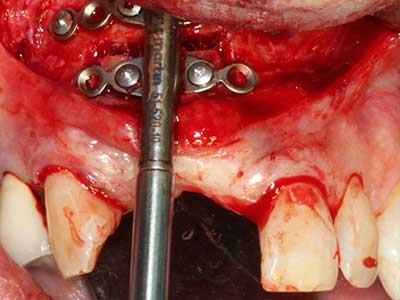

En la extracción de bloques óseos la piezocirugía también presenta ventajas adicionales: Además de la alta precisión en la osteotomía que ya se ha descrito antes, se ha comprobado que el uso de los delgados insertos de sierra resulta especialmente cuidadosas con el hueso. Frente a esto, sobre todo cuando se usan las fresas de Lindemann, cabe esperar pérdidas en la extracción significativamente más altas debido al mayor grosor de la parte frontal del cabezal (Lakshmiganthan, Gokulanathan et al. 2012). La separación basal que se necesita en particular en los injertos de bloque extraídos de forma retromolar se ve facilitada mediante sierras perpendiculares especialmente previstas a tal fin, lo que permite considerar que la cirugía piezoeléctrica es un procedimiento preciso y seguro para la obtención de bloques de hueso en el área retromolar (Happe 2007) (fig. 1-12).

El tejido óseo no solo tiene un contenido puramente mineral, sino que también presenta una importante proporción de fibras de colágeno. Esto no solo garantiza una buena resistencia a la presión, sino también una cierta flexibilidad, que puede aprovecharse para la realización de aumentos. En la plastia de expansión clásica a efectos de una partición ósea, la cresta maxilar atrofiada se divide en su eje longitudinal y, tras alcanzar una profundidad de osteotomía suficiente, se extiende con cuidado (fig. 13-16), en un caso ideal sin desperiostizar de forma visible el maxilar (Brugnami, Caiazzo et al. 2014, Stricker, Fleiner et al. 2014). Los sistemas de tornillos y placas con distancia de expansión creciente han demostrado su eficacia para distanciar entre sí las dos tablas óseas por debajo del umbral de rotura. Por regla general, se requieren anchuras de hueso residual de al menos 3 a 4 mm (Chiapasco, Zaniboni et al. 2006) para garantizar una flexibilidad y una cobertura ósea suficientes de los implantes que van a incorporarse. En caso necesario, una osteotomía de descarga vertical unilateral o bilateral puede mejorar la flexibilidad. Como alternativa a la técnica clásica se ha descrito una combinación con otras técnicas de aumento, sobre todo en la parte bucal.

Con el uso de sierras piezoeléctricas la división se efectúa de forma especialmente cuidadosa y sin pérdidas importantes de las dimensiones, por lo que no se han encontrado diferencias significativas entre los implantes realizados en el maxilar dividido y en la cresta alveolar no deficitaria (Chiapasco, Zaniboni et al. 2006, Danza, Guidi et al. 2009). No obstante, precisamente en la partición profunda y limitada de forma local, es preciso asegurarse de que exista una adecuada irrigación por agua para evitar que se produzcan sobrecargas térmicas en las áreas de osteotomía apical.